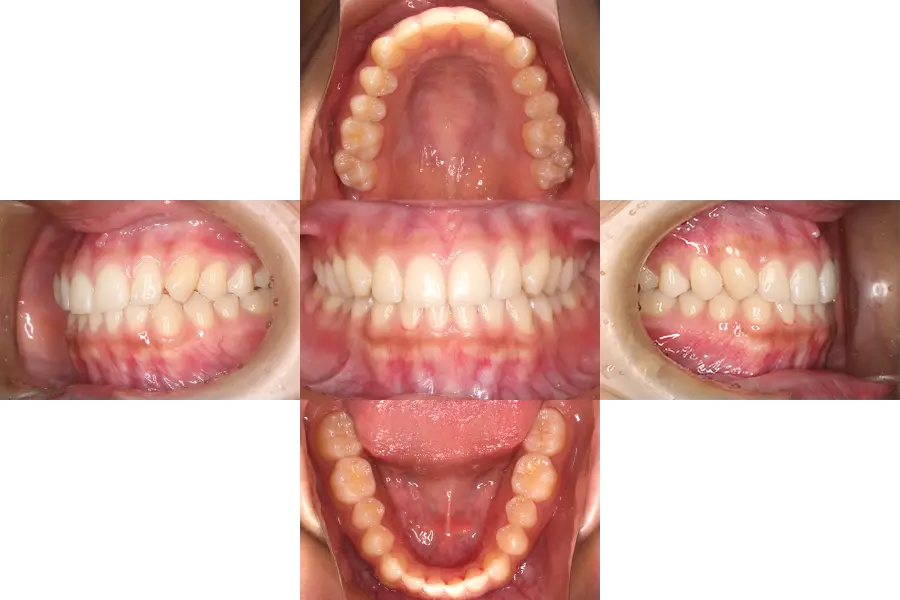

上顎前突の小児矯正治療例

- 主訴

- 前歯の凸凹、八重歯

- 治療開始年齢

- 10歳

- 診断

- 上顎前突、凸凹

- 難易度

- 中等度

- 使用した装置

- ヘッドギア、唇側ブラケット装置

- 治療期間

- 約1.0〜1.5年

- 費用(税込)

-

基本料金 399,300円 調整料(約12〜18回) 来院ごと6,600円 総額 498,300円~

- 治療について

治療開始時、上下顎共に狭く犬歯が生える隙間が全く無い状態だった。

そのため、始めに拡大装置にて上下顎歯列の拡大を行った後に、ブラケット装置をつけ隙間の確保および、上下のかみ合わせの改善を行った。

- 治療のリスク

違和感、痛み、しゃべりにくさ、虫歯のリスクの増大、歯磨きのしにくさ、ブラケット脱落の可能性。自費診療。